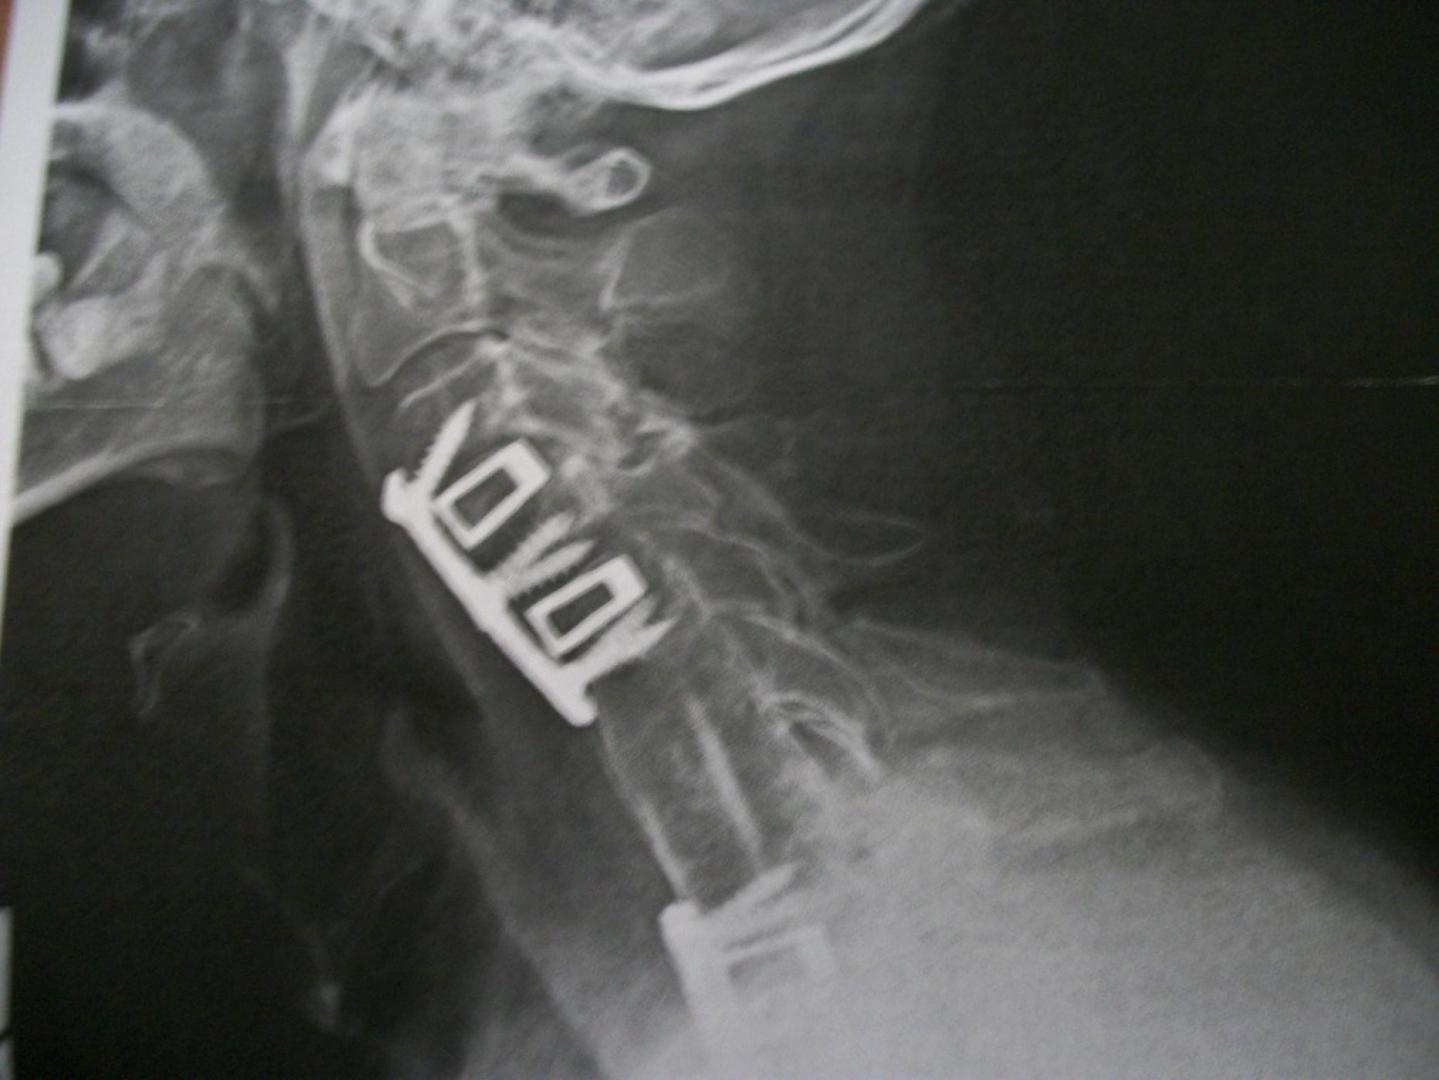

mod3l Lover Posted April 20, 2016 Author Posted April 20, 2016 (edited) Hey Kerry, Truth be told, they are the same old worn out hands, but they are working better again! 10 screws, and 3 titanium plates later. David S. Edited April 20, 2016 by mod3l Lover